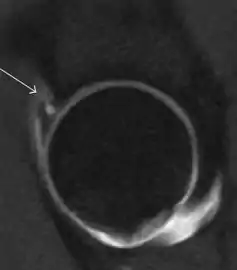

MRI has been shown to have 100% sensitivity and specificity in prospective studies of occult hip fractures. These fractures were diagnosed by bone marrow edema and a low signal fracture line, mainly on T1 or T2 weighted images (Figure 10).[1]

Figure 10:

Stress femoral neck fracture in a young athlete barely visible in X-ray film as a sclerotic line (arrow)[1]

In this case, Tc 99 scintigraphy shows a band of uptake[1]

Furthermore, T1 (left) and DP fat saturated (right) weighted MR images showed the fracture line and a pattern of edema.[1]